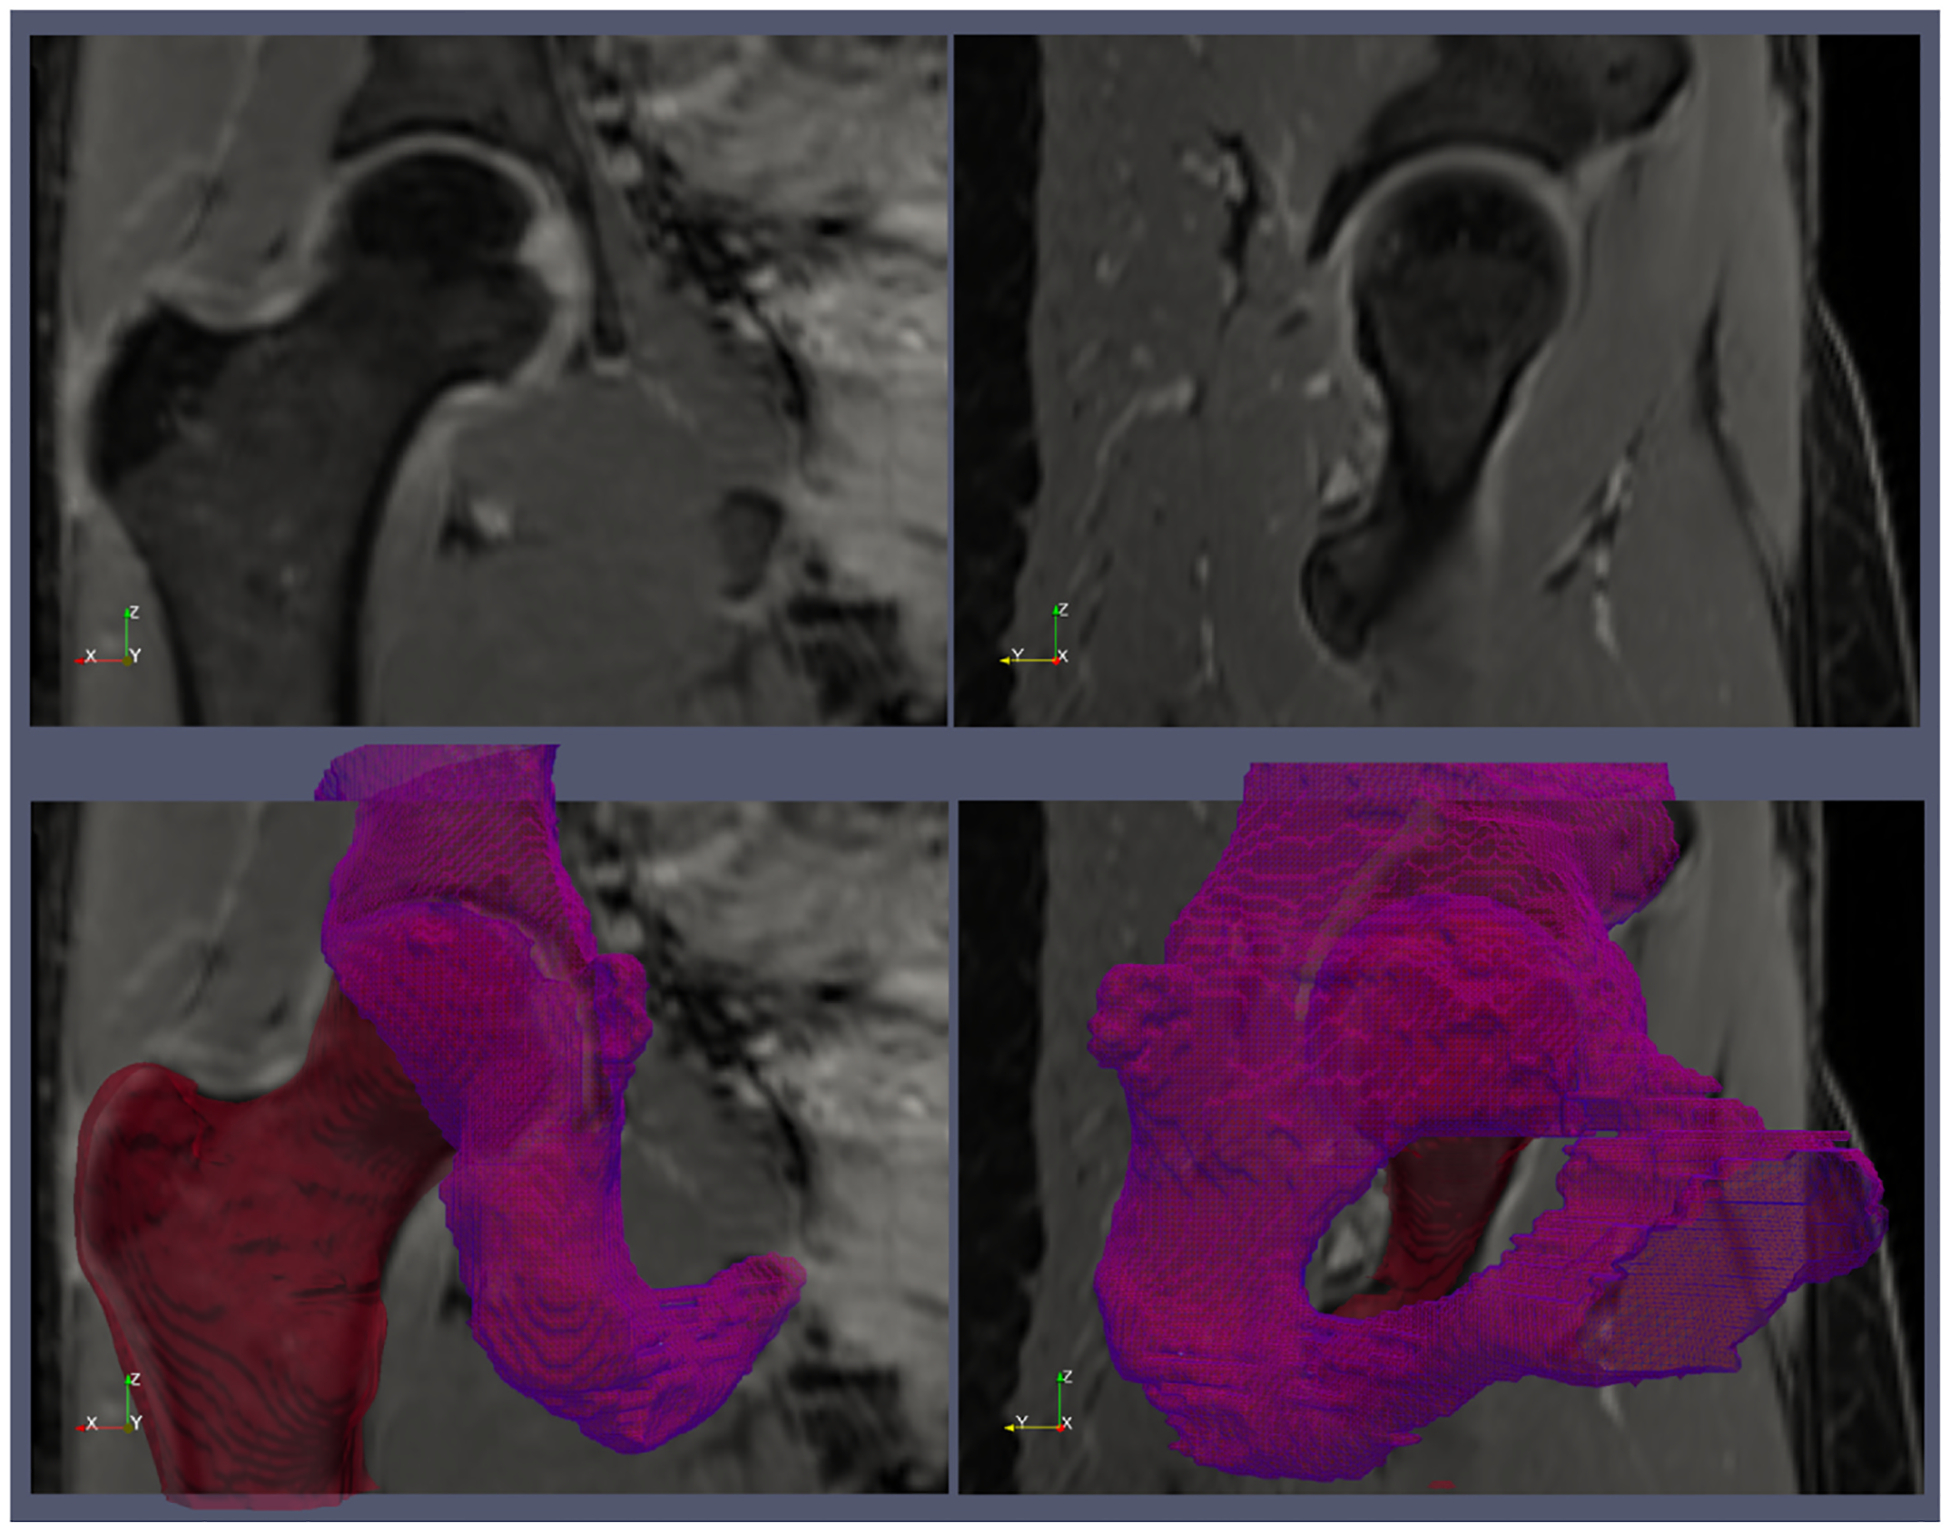

Fig. 1.

An example of the ground truth segmentation of the femur (red) and acetabulum (violet). The top row shows two water-only images from the Dixon MRI acquisition. The bottom row shows the 3D surfaces of the femur and acetabulum reconstructed from the regions of interests that were manually segmented on the MR images.